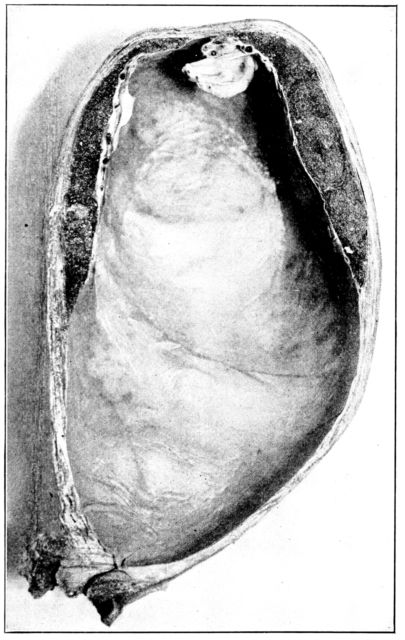

| 25. | Embryo about 5.5 cm. long in amniotic sac | 77 |

| 26. | Outlines of fetus at different stages | 78 |